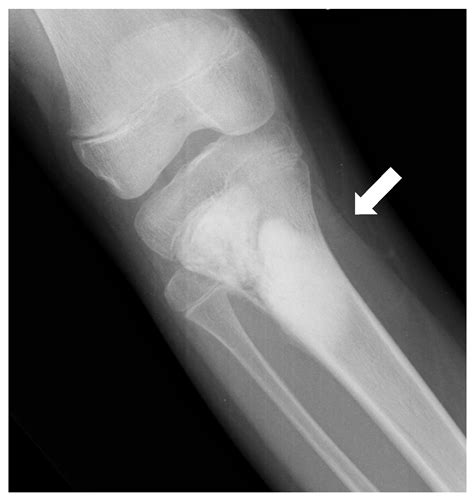

What makes this insidious is the tumor’s origin. Osteosarcoma arises in the epiphyseal cartilage—where bone growth meets soft tissue—often near the elbow or knee. This location, deep within the limb, delays pain signals from reaching the brain. Unlike acute fractures, the discomfort isn’t sharp; it’s a dull, persistent ache that escalates incrementally. By the time the dog resists jumping or favors a paw, the tumor may already be aggressive—often reaching stages where metastasis to the lungs is imminent.

What clinicians and researchers have learned in the last decade is that standard physical exams miss more than half of early osteosarcoma cases in Great Danes. Radiographs, while standard, detect bone destruction late—after the tumor has infiltrated. Advanced imaging, such as MRI or CT, reveals early cartilage changes and marrow edema up to 8 months before lameness becomes obvious. Yet, access to such diagnostics remains limited outside academic centers.

Compounding the challenge is the lack of breed-specific screening guidelines. While hip dysplasia has robust preventive protocols, osteosarcoma in Great Danes remains reactive. Some breeders now advocate for annual skeletal evaluations in puppies over 6 months old, but compliance is low. One breeder interviewed in 2023 described a 3-year-old Great Dane who limped for 5 weeks—attributed to “getting too rough”—before a CT scan revealed a tumor buried in the distal humerus.

Take the case of Maxim, a 21-month-old male Great Dane. His owner described a “slight limp” lasting 10 days post-run. Initially dismissed, follow-up vet visits revealed progressive stiffness. An MRI at a specialty clinic detected lytic bone lesions in the elbow—early osteosarcoma, stage I. Surgeons removed the tumor, and Maxim survived 18 months with aggressive therapy. Had the limp been recognized as a warning, he might have had a curative margin. Instead, the delay underscores a systemic gap: public awareness—and clinical vigilance—lag behind the biology of the disease.

For owners and vets alike, the lesson is clear: watch for the *disruption* of routine, not just the limp itself. A single missed mm of mobility, a fleeting favoring—each is a thread in a pattern that demands investigation. The bone may look normal on X-ray. The soft tissue, to the untrained eye, seems fine. But osteosarcoma thrives in silence, exploiting the gap between expectation and reality.